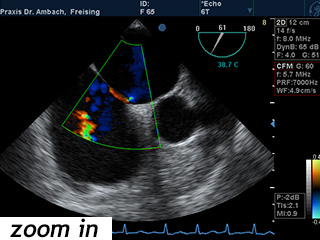

Die Echokardiographie, kurz "Echo", ist eine Ultraschalluntersuchung des Herzens, mit der insbesondere die Funktion des Herzmuskels und die Herzklappen untersucht werden können. Sie ist eine Standarduntersuchung bei fast allen Herzerkrankungen und ist ohne jegliche gesundheits- schädliche Einflüsse. Auch Auswirkungen eines hohen Blutdruckes auf den Herzmuskel lassen sich damit feststellen. Die hochtechnisierten Geräte hierfür nutzen den Dopplereffekt zur Geschwindigkeitsmessung der Blutströmung und stellen die Flussrichtung des Blutes farbcodiert dar.

TEE

Die transösophageale Echokardiographie ist eine Ultraschalluntersuchung des Herzens über eine Sonde in der Speiseröhre ("Schluckecho"). Von hier lassen sich die Strukturen des Herzens sehr viel genauer als von außen darstellen. Klappenerkrankungen oder Defekte in der Herzscheidewand lassen sich damit gut beurteilen. Auch nach Schlaganfällen wird diese Untersuchungsmethode eingesetzt, um mögliche Blutgerinnsel im Herzen zu lokalisieren.